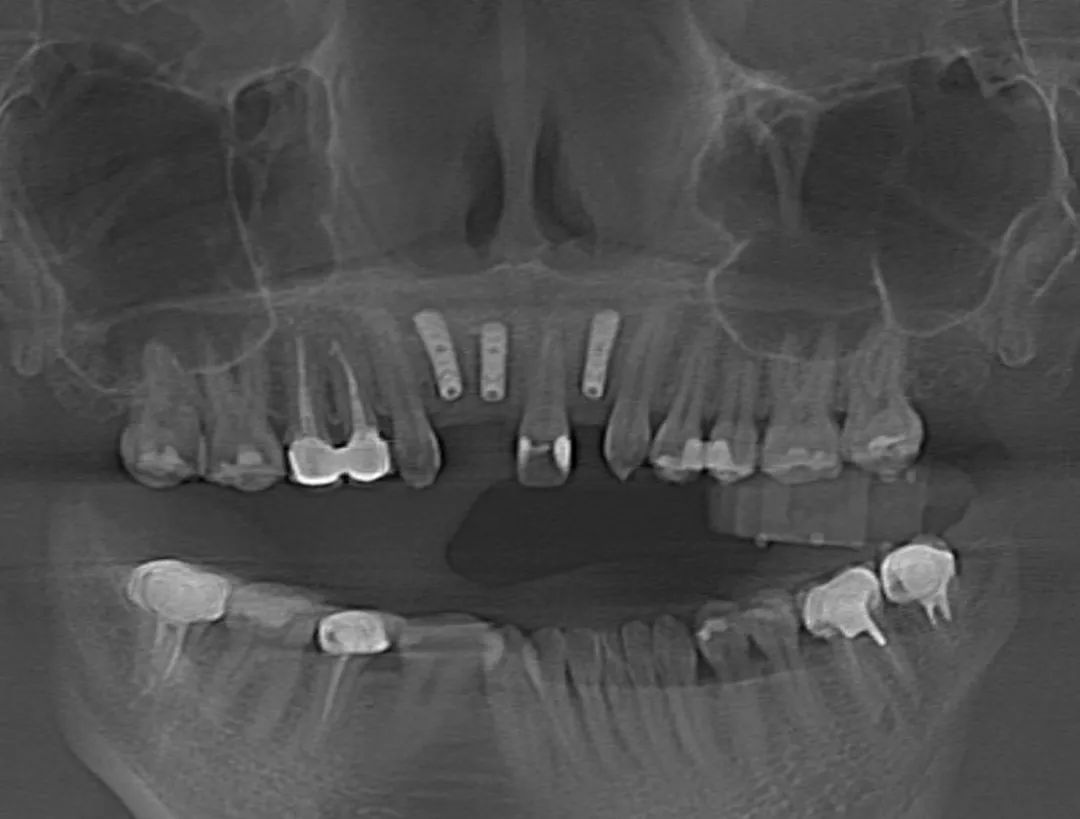

7月15日,瑞金醫(yī)院高益鳴主任團(tuán)隊(duì)實(shí)施了一例口腔手術(shù)機(jī)器人輔助下的上前牙美學(xué)區(qū)種植手術(shù),這是上海首例機(jī)器人輔助下的口腔種植手術(shù)。接受該手術(shù)的患者是一位年輕女性,她因意外事故導(dǎo)致前牙缺失,迫切希望能夠重拾笑容。高益鳴主任詳細(xì)了解她的病史及美學(xué)訴求,決定采用數(shù)字化技術(shù),為她訂制個(gè)性化種植方案。以往,前牙美學(xué)區(qū)的種植及修復(fù)只能依靠醫(yī)生的臨床經(jīng)驗(yàn),簡(jiǎn)單來(lái)講就是“手感”,但前牙美學(xué)區(qū)對(duì)術(shù)者技術(shù)要求極高,若是出現(xiàn)毫米級(jí)偏差,就無(wú)法達(dá)到理想的粉白美學(xué)(修復(fù)后的牙冠和牙齦美學(xué)指數(shù))效果,還會(huì)導(dǎo)致牙齦萎縮、種植體頸部暴露等諸多問(wèn)題。口腔手術(shù)機(jī)器人對(duì)此提出了新的解決方案,它可以通過(guò)術(shù)前可視化體外模擬,術(shù)中精準(zhǔn)定位、動(dòng)態(tài)導(dǎo)航、人機(jī)隨動(dòng)等功能,極大提升種植手術(shù)的精度和質(zhì)量。醫(yī)生可以借助口腔手術(shù)機(jī)器人,精準(zhǔn)完成口腔種植手術(shù),縮短手術(shù)時(shí)間,實(shí)現(xiàn)標(biāo)準(zhǔn)化種植。

術(shù)前,醫(yī)生將患者的影像學(xué)資料導(dǎo)入機(jī)器人系統(tǒng),進(jìn)行種植體植入全過(guò)程的體外可視化模擬,這樣手術(shù)團(tuán)隊(duì)能充分了解患者牙槽骨的骨量及解剖結(jié)構(gòu)走向,更詳盡地制訂手術(shù)方案。術(shù)中,高益鳴主任、李小曼醫(yī)生共同按既定方案,在機(jī)器人全自動(dòng)模式下,精準(zhǔn)標(biāo)定種植位點(diǎn)并逐級(jí)擴(kuò)孔備洞。而且,機(jī)械臂的減速區(qū)設(shè)定,讓機(jī)器人在入口時(shí)動(dòng)作不會(huì)過(guò)快,“溫柔”且“迅速”地有序按照指令進(jìn)行手術(shù)。手術(shù)過(guò)程相比傳統(tǒng)方式來(lái)說(shuō)縮短了近一半。如今,這位女士恢復(fù)良好。